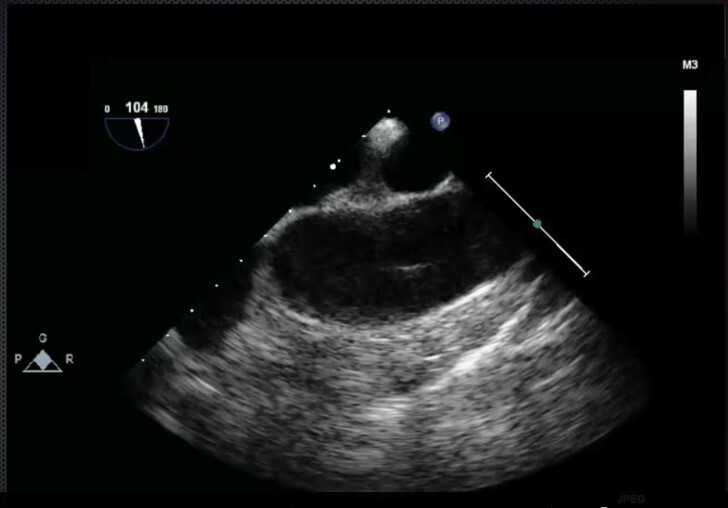

Mid-Esophageal 2 chamber view. Multiplane to between 80-100 degrees.

Structures: LA, LV, coronary sinus, L atrial appendage